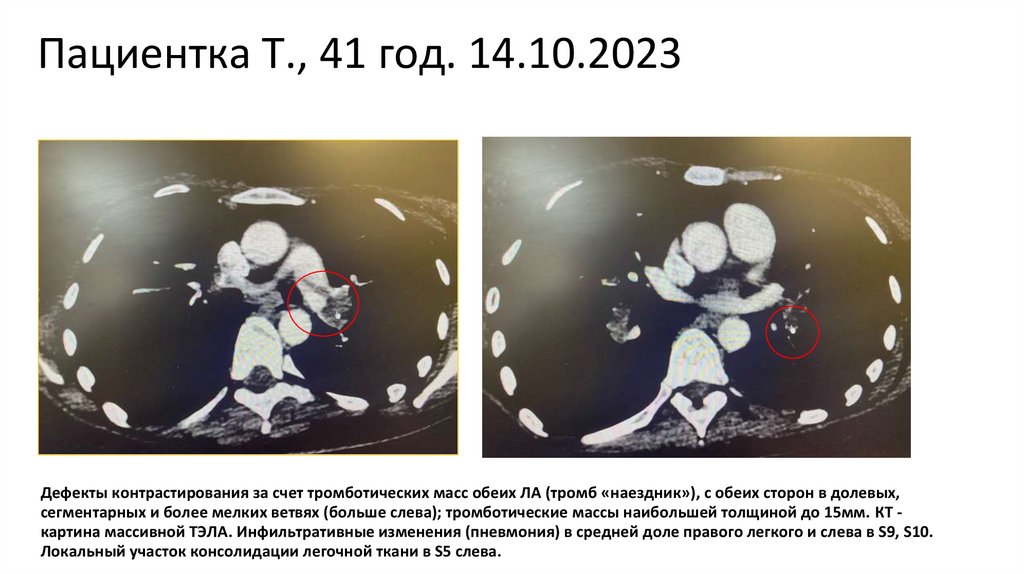

Пациентка Т., 41 год. 14.10.2023

Дефекты контрастирования за счет тромботических масс обеих ЛА (тромб «наездник»), с обеих сторон в долевых,

сегментарных и более мелких ветвях (больше слева); тромботические массы наибольшей толщиной до 15мм. КТ картина массивной ТЭЛА. Инфильтративные изменения (пневмония) в средней доле правого легкого и слева в S9, S10.

Локальный участок консолидации легочной ткани в S5 cлева.